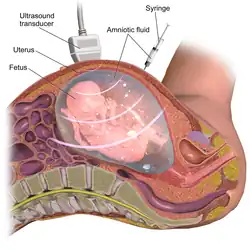

There are various types of genetic testing that can be used to confirm an L1 syndrome diagnosis in a patient.[2] After birth, genetic tests carry a low-risk of physical complications and are minimally-painful: for the patient, the process requires a small amount of blood being drawn from the arm using a needle.[32] However, prenatal genetic testing carries significant risks for both the fetus and mother due to the need to remove genetic material from the fetus while it is still in utero.[33] In order to conduct prenatal genetic testing, the mother and fetus must undergo either amniocentesis (the surgical puncturing of the amniotic sac, which holds the fetus in the womb) or, less frequently, chorionic villus sampling.[34] Amniocentesis provides a sample of amniotic fluid that can be used to screen for sequence variants or chromosomal variants,[35] whereas samples obtained through chorionic villus sampling can only be used to detect major chromosomal abnormalities (such as trisomy 21),[36] making chorionic villous sampling less relevant in the context of diagnosing L1 syndrome (which is often caused by sequence variants).[37] Amniocentesis (typically performed between 15 and 18 weeks of pregnancy) has a 1% risk of complications for mother and fetus, including miscarriage, while chorionic villus sampling (typically performed between 10 and 12 weeks of pregnancy) has a 2% risk of complications including miscarriage.[33] Mothers carrying a fetus with suspected L1 syndrome will often elect to undergo amniocentesis despite its risk, rather than waiting to pursue lower-risk genetic testing after their child is born, because prenatal diagnostic results can inform considerations to terminate the pregnancy.[38][39]